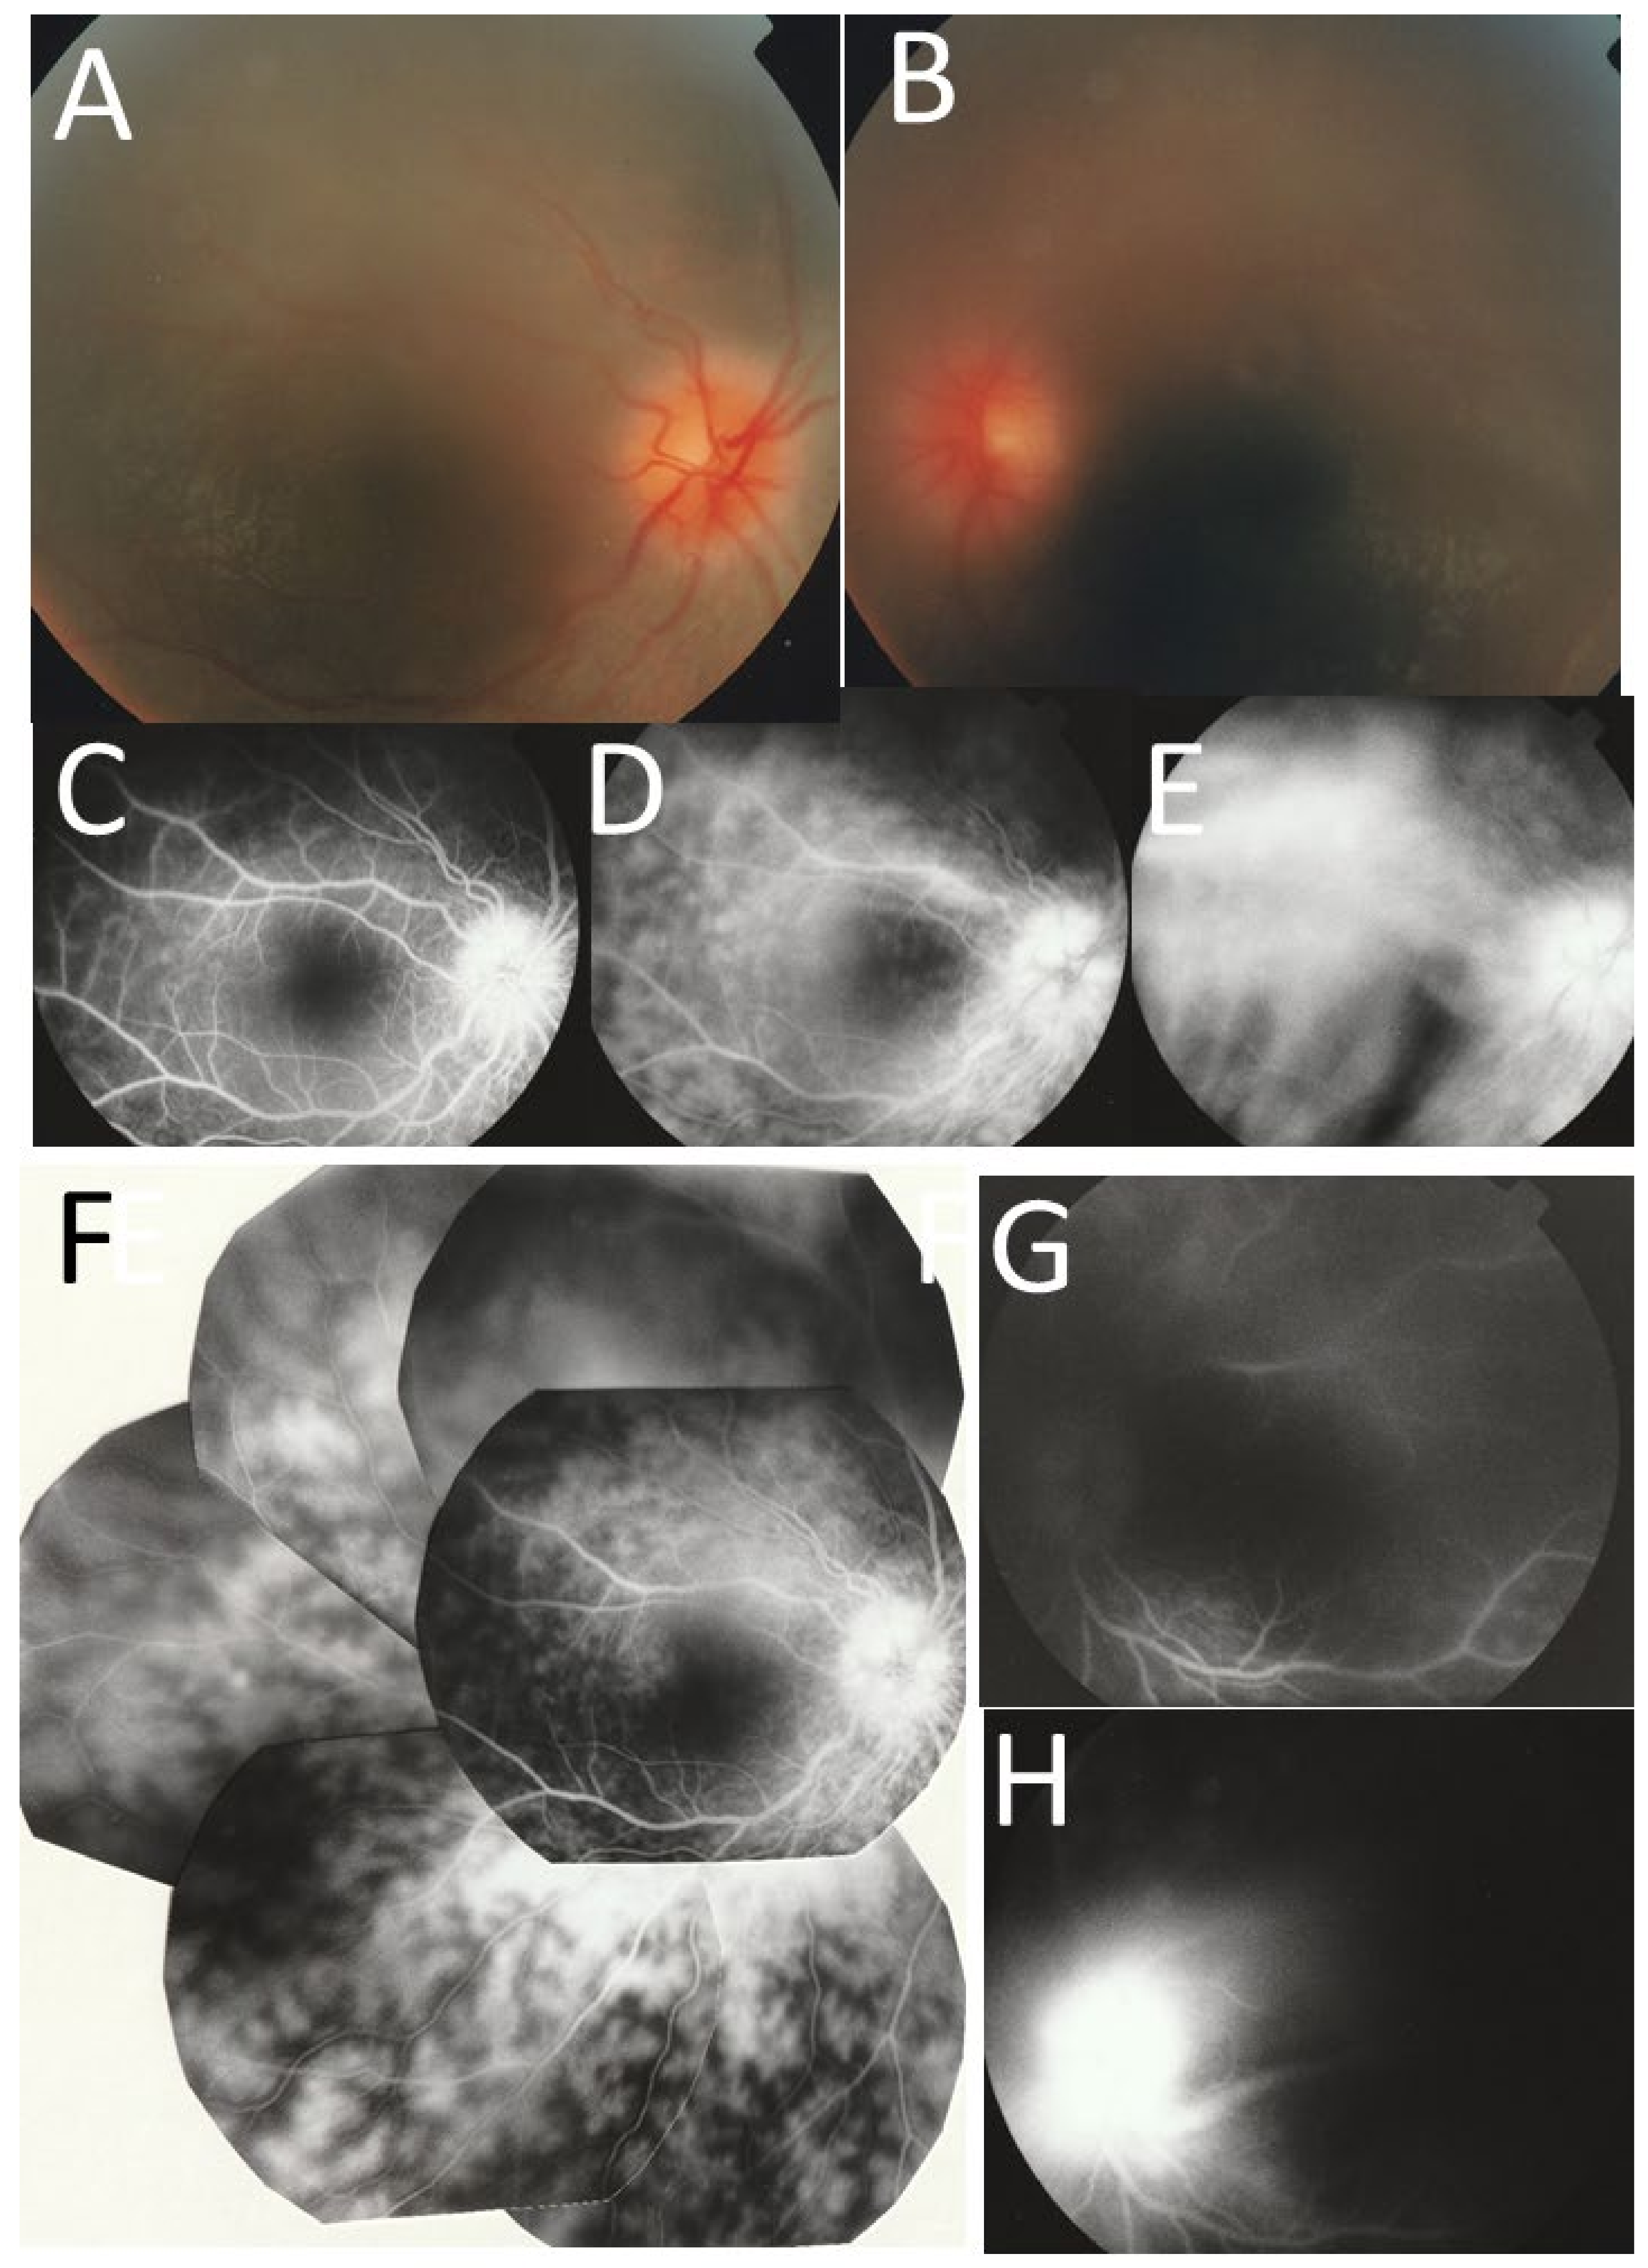

2. Case Reports

2.1. Case 1

2.2. Case 2

2.3. Case 3